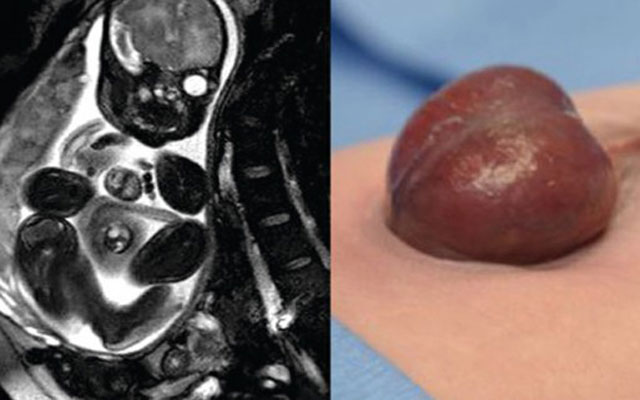

- تتعافى الطفلة الاميركية “أودريانا كاردينيز” في مستشفى الأطفال في ولاية تكساس بعد أن ولدت قبل موعدها بخمسة أسابيع مع حالة نادرة تسمى “انتباذ القلب” وهو تشوه خلقي يكون فيه القلب خارج القفص الصدري إما جزئياً أو كلياً.

وذكرت صحيفة “الشرق” السعودية ان الطفلة خضعت لعملية خطيرة جداً لإنقاذ حياتها ،حيث قام فريق من الجراحين بإجراء العملية المعقدة لها لإعادة القلب إلى صدرها.

يذكر ان ثمانية من مليون طفل يولدون بذلك التشوه الخلقي، و90% من الأطفال يكونون إما خدجا أو يموتون بعد ثلاثة أيام من ولادتهم